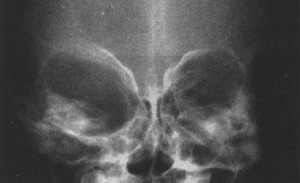

5、X線拍片,僅少數可見眶腔擴大,常無骨質破壞,多數有副鼻竇炎。有者可見眶內骨膜增厚,眶骨增生等現象。

3、X線拍片,僅少數可見眶腔擴大,常無骨質破壞,多數有副鼻竇炎。有者可見眶內骨膜增厚,眶骨增生等現象。